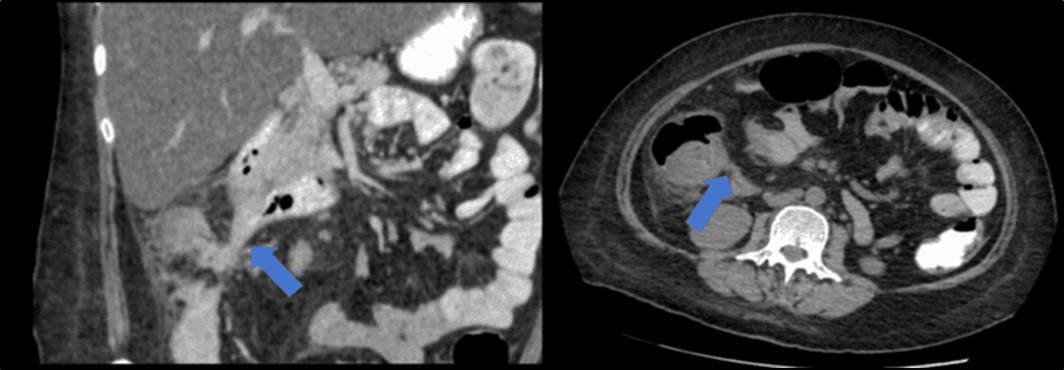

There was no evidence of malignancy or IBD seen during both endoscopic procedures. Computed tomography (CT) scan of the whole abdomen was done which showed inflammatory changes involving the cecum and adjacent duodenum and ileum with coloenteric fistulae. There was noted progression of abdominal lymphadenopathies as well as ascites. Main consideration was an infectious disease process (i.e. TB) (Figure 2, Figure 3, Figure 4 to Figure 5).

Figure 3.Coronal and axial view of the abdomen, the blue arrows pointing towards the suggestive communication to the ileum.

Figure 4.Coronal and axial view of the abdomen, the blue arrows pointing towards the suggestive communication to the duodenum